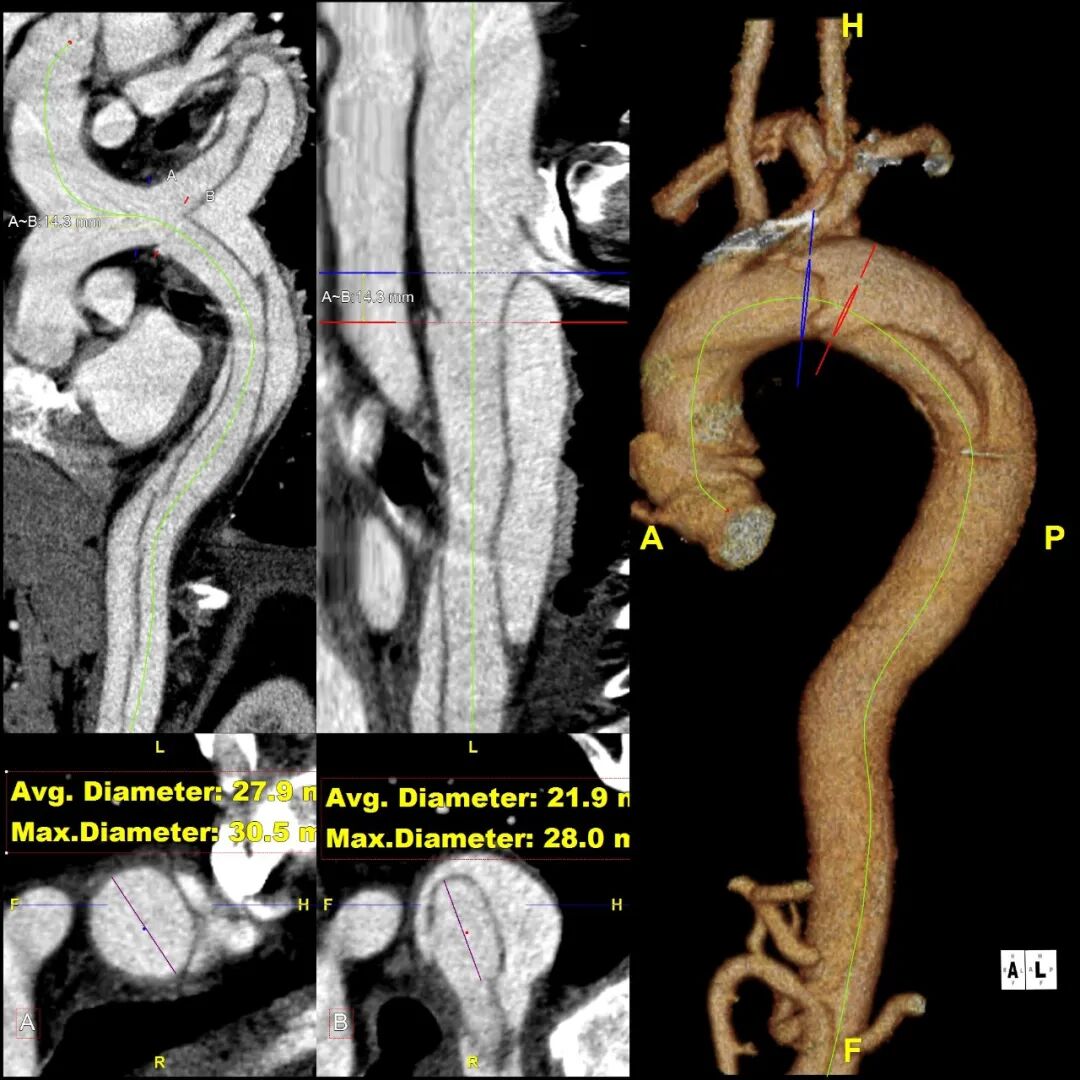

患者 10月前因“梗阻性黄疸、胆总管结石”检查发现主动脉夹层B型,否认腹痛、腰背痛,追问病史,2019年曾出现胸痛,行冠脉造影未见异常,当时血压170mmHg。诊断为:B型主动脉夹层累及到LSA后缘,左侧椎动脉发自于主动脉弓上的变异解剖形态

1.术前VS术后(CTA 横断面对比)

正位造影:左椎动脉起至主动脉弓,弓上四分支显影好,双侧椎动脉显影,左前55度造影:自左锁骨下动脉开口5mm处降主动脉可见小破口,标记左颈总、左锁骨下动脉,破口、小弯侧拐角。交换Lunderquist导丝并控制血压到100mmHg,导入20F鞘,导入GORE® TAG® 可主动调控胸主动脉覆膜支架(31-31-200mm)到靶病变,将支架覆膜开始部分定位于左锁骨下动脉开口中段释放,经造影评估后,微调支架位置和小弯侧贴附后,二次拉线释放。最后,造影显示降主动脉血流通畅,支架形态好,支架完全封堵原发破口,左颈动脉血流通畅,左锁骨下动脉通畅,未见内漏。

3.术前VS术后(3D影像)